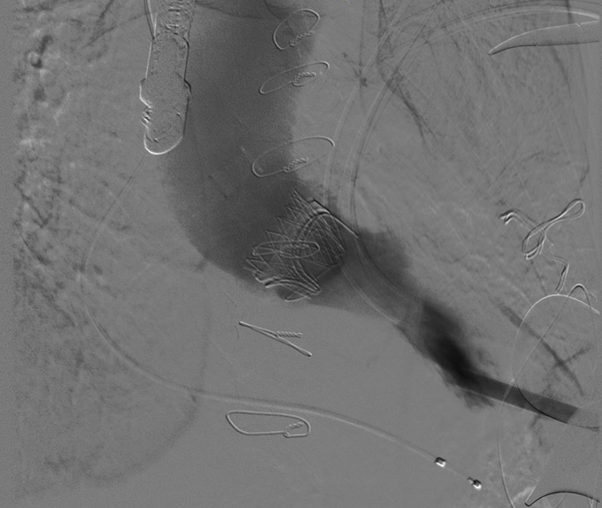

术中,团队定位准确、操作细致并将瓣膜精准释放至指定位置。经食道超声测得二尖瓣跨瓣压差从入院时的29mmHg下降至5mmHg,人工二尖瓣形态及功能良好。从切皮到缝合仅用时约2小时。术后第三天叶大爷胸闷气促等症状就得到了明显改善,顺利康复出院。

近年来,心脏疾病手术治疗技术不断发展,尤其对于需再次手术的患者, 心血管外一科团队根据患者个体情况选择经皮(股)或经心尖途径给予患者最佳的手术治疗。此次“经心尖二尖瓣瓣中瓣生物瓣膜植入术TMVI(VIV)”使用导管介入的方法将人工瓣膜在体外压缩装载到输送系统,沿着血管路径或者穿心尖,送达患者二尖瓣瓣环处,并将人工瓣膜释放固定在二尖瓣瓣环内替换原有瓣膜。